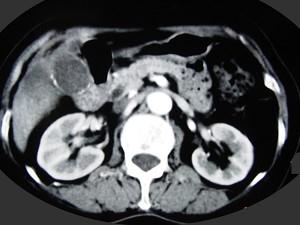

问题 女,66岁,右上腹痛,发热伴有黄疸两月余,消瘦、纳差,影像检查如图,最可能的诊断是 ( )

选项 A、肝内胆管细胞癌 B、胆囊癌及原发性肝癌 C、胆囊结石及肝血管瘤 D、胆囊癌肝转移 E、胆囊结石及脂肪肝

答案 D